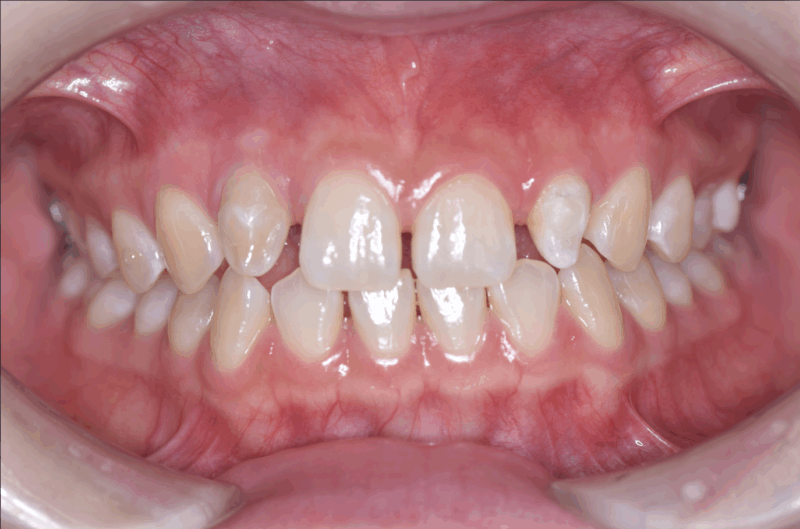

【初診時口腔内写真】

画像の左上の歯茎に腫脹と発赤が認められます。

初診時に認められていた左上の腫脹と発赤は改善し、認められなくなりました。